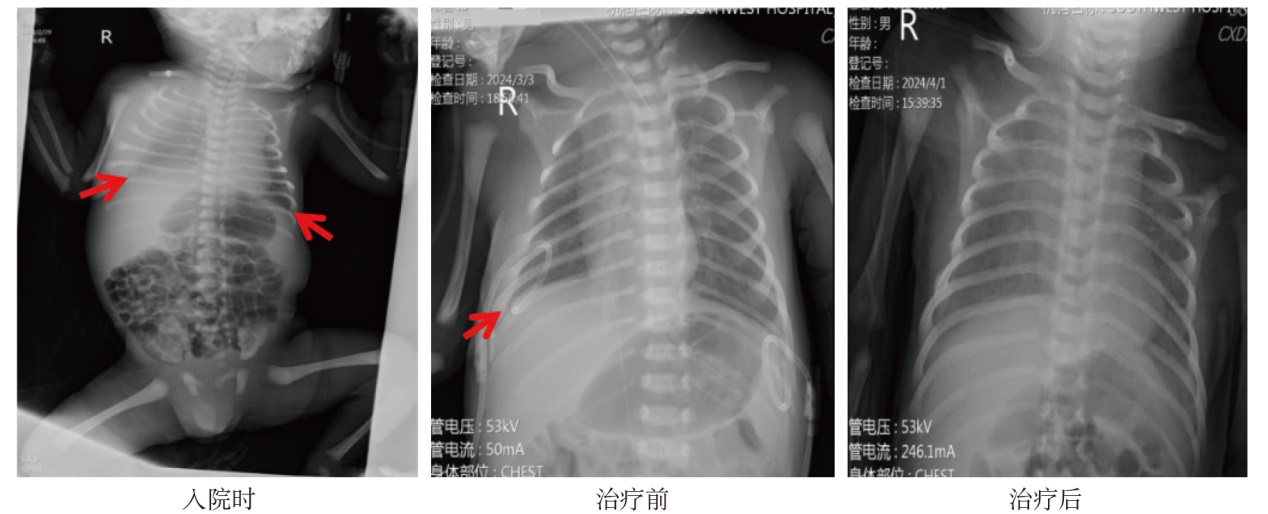

ZHENG Ruixue, SUN Xiaodong, WU Guilan, SHEN Leilei. Neonatal refractory congenital chylothorax: two case reports and literature review[J].Journal of Clinical Pediatrics, 2025, 43(10): 775-781.